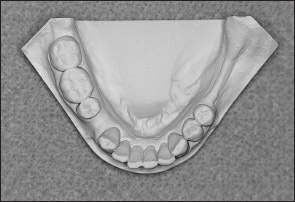

• Kennedy Class II arch: Displays a unilateral edentulous area located posterior to the remaining natural teeth (Figs 1-13 and 1-14).

Fig 1-14 Mandibular Kennedy Class II arch.